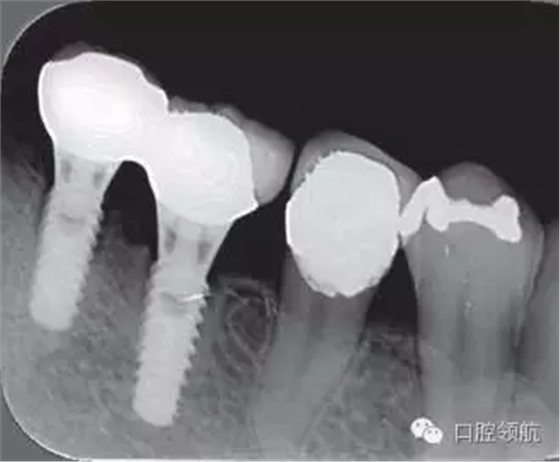

2005年4月時,可見(左下第6顆牙) 部的種植體達到第4螺紋,(左下第7顆牙)的種植體周圍觀察到位于第3螺紋的頸部進行性骨吸收(圖4)。到2009年9月時,骨吸收像的周圍有了明顯的骨密度增加影像(圖5)。

圖4 (左下第6顆牙)的種植體達到第4螺紋, 7 的種植體達到第3螺紋的頸部進行性骨吸收現(xiàn)象(2005年4月)。